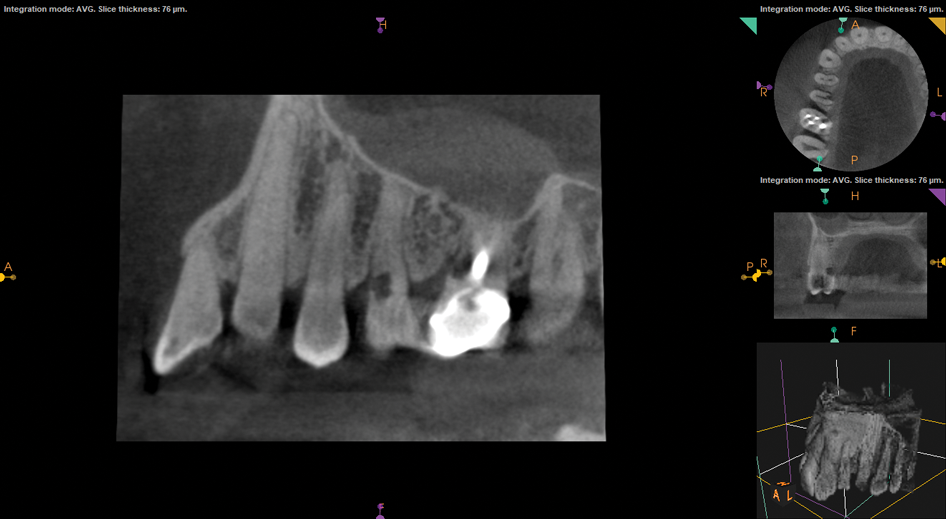

(1.) Preoperative CBCT scan showing Class 2 ECR defects on teeth Nos. 3 and 4 that were surgically accessible.

Figure 1

If an ECR lesion is surgically accessible, external repair with gingival flap surgery is the treatment of choice (Figure 1 through Figure 6). When considering external repair, clinicians should evaluate each case for potential postoperative esthetic concerns, such as the possibility of recession following surgical repair.6,7 Moreover, clinicians should assess the overall restorability of affected teeth because the surgical repair of large ECR lesions may predispose them to fracture.6 When a Heithersay Class 1 lesion is diagnosed, nonsurgical root canal therapy (NSRCT) in addition to the surgical repair is often unnecessary. However, in Heithersay Class 2 or larger defects where pulpal involvement is suspected or confirmed, NSRCT may be necessary in addition to surgical repair.6 If NSRCT is indicated in addition to surgical repair, it is recommended that it be completed prior to surgery to avoid exacerbating pulpal disease.

If an ECR lesion is inaccessible externally or internally, and it is neither symptomatic nor associated with pathologic bone loss, active monitoring represents a reasonable treatment alternative. This is frequently the treatment of choice for patients presenting with Heithersay Class 4 ECR defects or truly inaccessible Class 2 or Class 3 defects. Annual reevaluation is recommended for these patients, and the use of cone-beam computed tomography (CBCT) imaging should be considered.5,16